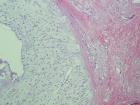

54 year old male with two year history of increasing swelling in left flank

Zoom image: Cell stain Cell stain.